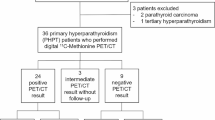

11C-methionine PET/CT was performed in 18 patients (11 women and 7 men, aged 42–79 years; mean age 57.8 years) on haemodialysis for renal failure (2–14 years’ duration), with normo-, hypo- or hypercalcaemia and HPT not localised by either dual-tracer 99mTc-pertechnetate/99mTc-sestamibi subtraction scans or dual-phase 99mTc-sestamibi scans.

In three of ten patients with normo- or hypocalcaemic HPT there was increased 11C-methionine accumulation in one gland. Seven of eight patients with hypercalcaemic HPT showed increased uptake: in five of these patients increased 11C-methionine accumulation was present in one gland, while in two it was demonstrated in two glands. All patients also had high-resolution ultrasound of the neck and were treated with subtotal parathyroidectomy, leaving a remnant of the smallest of the four glands. Regardless of their size, all glands with abnormal 11C-methionine parathyroid uptake were removed, and all demonstrated parathyroid hyperplasia. All patients developed post-parathyroidectomy hypoparathyroidism and one patient with normocalcaemic HPT relapsed 8 months after surgery.

Eighteen patients [11 women and 7 men, aged 42–79 years (mean 57.8 years)] with non-primary hyperparathyroidism were studied with 11C-methionine PET/CT scans. The study was approved by the Human Experimentation Committee (IRB), and each patient provided written informed consent prior to PET/CT. Ten patients had normo- or hypocalcaemic hyperparathyroidism and eight, hypercalcaemic hyperparathyroidism, the diagnosis being made on the basis of the relationship between serum calcium and parathyroid hormone levels (Table 1). All patients had been treated with haemodialysis for renal failure for 2–14 years.

Serum calcium levels were normal or low (mean 8.9 mg/dl, range 7.8–10.1 mg/dl) and parathyroid hormone levels were elevated (mean 705 pg/ml, range 290–1,900 pg/ml) in 10 of 18 patients, while in 8 of 18 patients both calcium and parathyroid hormone levels were elevated (mean 11.8 mg/dl, range 11.0–12.6 mg/dl, and 306 pg/ml, range 124–478 pg/ml, respectively) (Table 1).

Among the 18 patients, high-resolution ultrasound identified two enlarged parathyroid glands in 11, three glands in six and four enlarged glands in one (Table 1). In ten of the 18 patients (55.5%), PET/CT demonstrated abnormal accumulation of 11C-methionine (one parathyroid gland in eight patients and two glands in two patients) (Table 1). Mean SUV(parathyroid tissue/cervical soft tissue) was 3.3 (range 2.1–4.9) and mean SUV(parathyroid tissue/thyroid tissue) was 2.5 (range 1.5–3.6). There was no significant difference in parathyroid gland 11C-methionine SUVs between the group with normal or low calcium levels and the group with hypercalcaemic hyperparathyroidism. It is of note that in patients with normo- or hypocalcaemic hyperparathyroidism, 11C-methionine PET/CT identified one abnormal gland in only three of ten patients (30%), while in the group with hypercalcaemic hyperparathyroidism, seven of eight patients (87.5%) had abnormal 11C-methionine PET/CT (p<0.01 by χ2 test). Of the latter seven patients, five had one abnormal gland (Figs. 1, 2) and two, two abnormal glands on PET/CT. The significant difference observed in the rate of detection of abnormal parathyroid glands at 11C-methionine PET/CT in the group of normo- or hypocalcaemic patients versus the group of hypercalcaemic patients might be explained by the fact that in hypercalcaemic patients, that is patients more likely to be affected by tertiary hyperparathyroidism, autonomous parathyroid glands could be biologically more active in trapping 11C-methionine. Further, in four of the ten patients (40%) with abnormal 11C-methionine PET/CT scans (all of whom had hypercalcaemic hyperparathyroidism), the largest parathyroid gland seen on high-resolution ultrasound did not demonstrate the highest 11C-methionine avidity. Comparisons of SUV with serum calcium and parathyroid hormone levels and parathyroid gland weight by regression analysis did not reveal statistically significant differences. No patient had co-existing thyroid nodules in the present series.